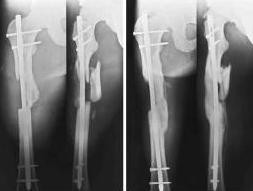

жесткой фиксации")и картинки в ряде классических руководств (вложеннный рисунок)

А вот если дать раннюю нагрузку на мыщелковые переломы бедра, может случится беда.

>>>Просто перештифтуйте ЗАКРЫТО более массивным штифтом, с рассверливанием и заблокируйте динамично.

А вот это до полной консолидации мыщелков сложновато. надо сначала влезть в коленный сустав, удалить гвоздь, выполнить ретроградное рассверливание и введение толстого штифта, не развалив при этом мыщелки. Коленка может "обидиться" на повоторное штифтование. Если штифтовать антеградно опять возникает вопрос: надо ли предварительно фиксировать мыщелки винтами?

В ведении даннного больного важно, если консолидация не наступает в ожидаемые сроки, своевременно поменять имплантат до его поломки. имплантатов